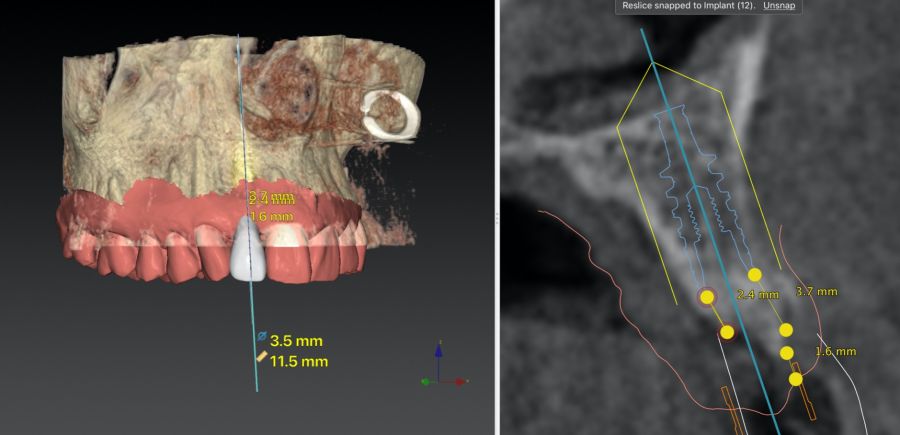

-Fase II: la cicatrización transcurrió sin complicaciones. Tras 5 meses de la cirugía de preservación alveolar, se planificó la cirugía implantológica guiada en posición 1.2 (Figura 2). Para ello, se utilizaron un archivo DICOM procedente de la tomografía computarizada de haz cónico (CBCT) y el archivo STL procedente del escaneado mediante un escáner óptico intraoral. Con esta información se construyó una férula quirúrgica de soporte dental (Figura 3). La férula quirúrgica se ancló sobre los dientes y guió la realización del lecho implantario y la colocación del implante. La técnica quirúrgica de cirugía guiada consistió en una cirugía con colgajo, preparando e insertando el implante (3,5 x 11,5 mm) según el protocolo estandarizado de cirugía guiada Nobel Active® (Nobel Biocare AB, Gothenburg, Sweden). Una vez colocado el implante 1.2, se obtuvo un injerto gingival compuesto de epitelio y tejido conectivo de la mucosa masticatoria palatina. A continuación, se realizó la desepitelización de la capa superficial de dicho injerto fuera de boca mediante una hoja de bisturí 15C con la finalidad de obtener un injerto de tejido conectivo de la capa subyacente18.